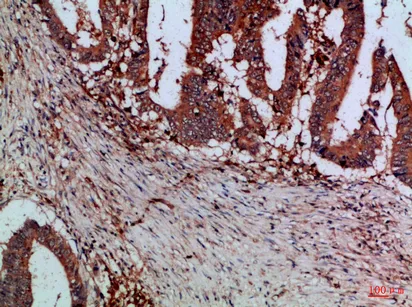

Mammaglobin A Rabbit Polyclonal Antibody

Cat: APRab13614

Size1:50μl Price1:$118

Size2:100μl Price2:$220

Size3:500μl Price3:$980